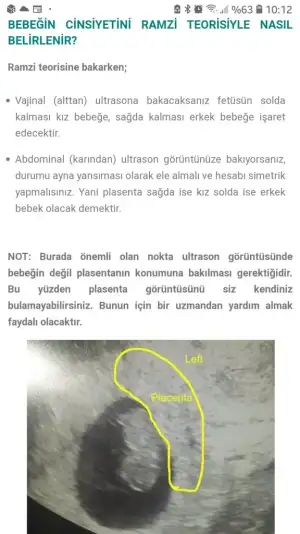

Ramzi teorisine göre diyor

yaa ama burda karındada vajinaldede bebek soldaysa kız diyo plesanta sagdaysa erkek diyoRamzi teorisine göre diyor